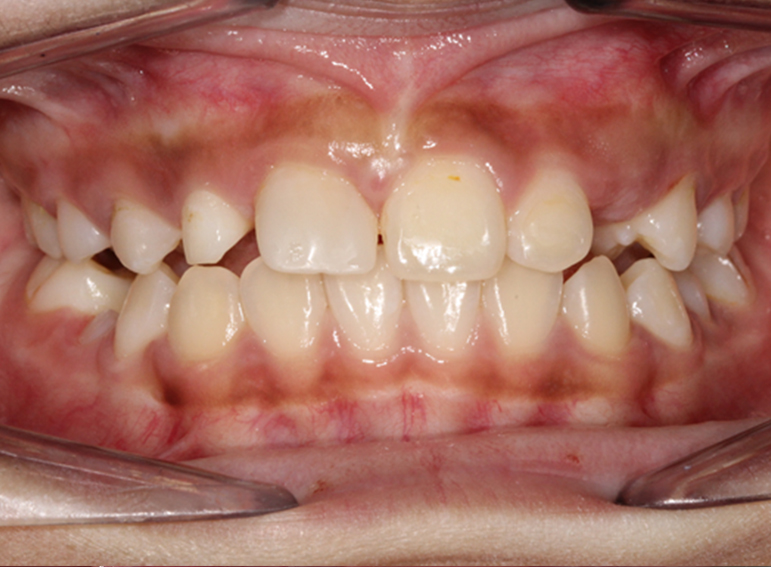

Replacement of 2 lateral incisors in a patient with hypodontia.